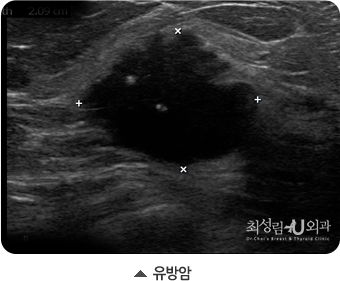

악성 종양 (유방암)

초음파에서 유방암은 보통 혹의 모양이 불규칙하거나, 경계가 불분명하게 보입니다. 물론 경계가 매끄러운 암도 있기 떄문에

양성종양처럼 보이더라도 크기가 크거나 점점 커지고, 만저지는 경우에는 조직검사를 실시해서 정확히 진단을 받아야합니다.